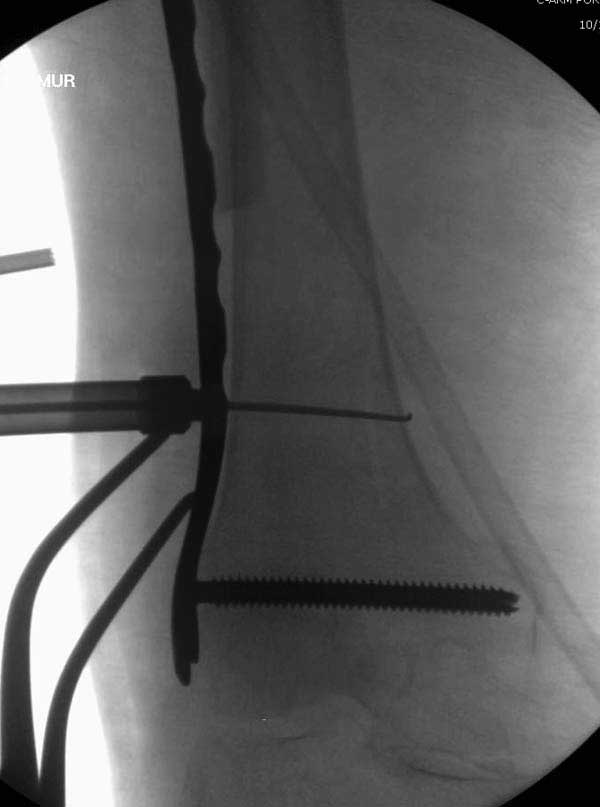

Повторно поступает после двух с половиной лет, где обнаруживается перелом на второй стороне. Немного сложно, но для фиксации выбрали Antegrade InterTan Smith Nephew Nail и с момента фиксации более 3х мес.